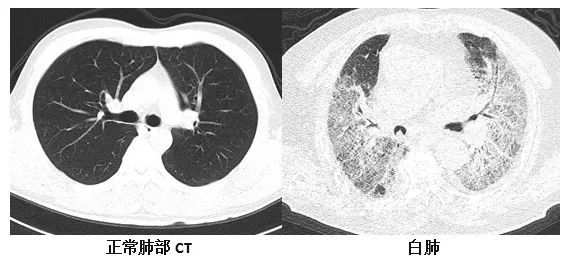

复旦大学附属华山医院感染科副主任医师张继明介绍,正常情况下,肺部主要是由充满了空气的肺泡组成,进行CT或者是X线检查时,射线可以很容易地穿透肺泡,在影像学上显示为黑色区域;当肺部受到病原体感染、临床上表现为重型肺炎时,患者肺泡里会出现炎症、渗出或实变时,射线不容易穿透病变区域,在影像学就出现了白色的区域。当白色区域面积达到了70%-80%时,临床上俗称其为“白肺”。事实上,“白肺”患者,其肺组织肉眼下看并不是白色的。

他表示,“白肺”是肺组织炎症渗出、肺实变所导致的一种影像学表现,“白肺”患者常常病情较为严重,预后较差。